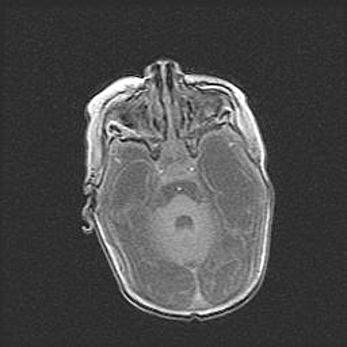

Церебральная ишемия II.

Возраст: 7 дней

Вес: 3350 г

Пол: женский

Окружность головы: 35 см

Срок гестации: 39 недель

Ишемия головного мозга – это состояние, которое развивается в ответ на кислородное голодание вследствие недостаточного мозгового кровообращения. У новорожденных она является следствием дефицита кислорода, что ведет к метаболическим расстройствам различной степени тяжести в тканях головного мозга, в том числе к развитию коагуляционных некрозов и гибели нейронов.